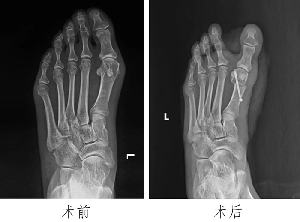

足踝外科:微創(chuàng)技術(shù)顯身手,造福患者除病痛

近年來,微創(chuàng)技術(shù)在外科領(lǐng)域應(yīng)用日益廣泛。微創(chuàng)技術(shù)通過特殊的手術(shù)入路,應(yīng)用特殊的器械設(shè)備,比傳統(tǒng)方法創(chuàng)傷更小、精準(zhǔn)度更高,具有創(chuàng)口小、疼痛輕、出血少、恢復(fù)快、住院時(shí)間短等優(yōu)勢。我院足踝外科成立以來,通過讓年輕醫(yī)生走出去、請進(jìn)來等舉措,學(xué)習(xí)引進(jìn)多種技術(shù),在科主任潘維亮的指引下,像徐潭潭、范明生、張亞州等